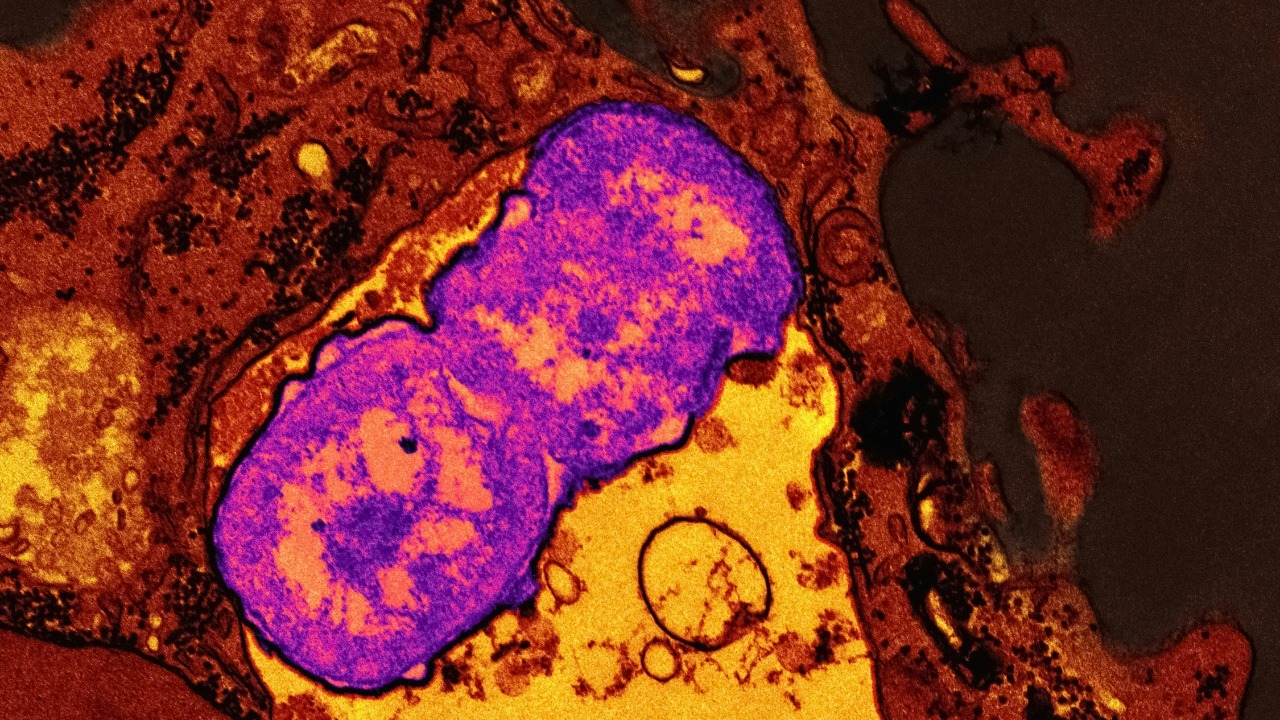

Why cancer returns years later, and how we can stop it

Read More: Why cancer returns years later, and how we can stop itCancer’s cruelest trick is its ability to disappear, only to reappear years later in a new organ or a familiar…